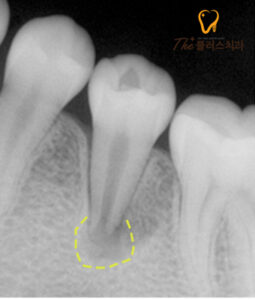

환자분의 정확한 상태를 알아보기 위해

먼저 X-ray 촬영을 진행하였는데요.

정상적으로 닫혀있는 치근의 모양이 아닌

근관이 열려있는 형태의

기형치로 염증이 발생해 있었습니다.